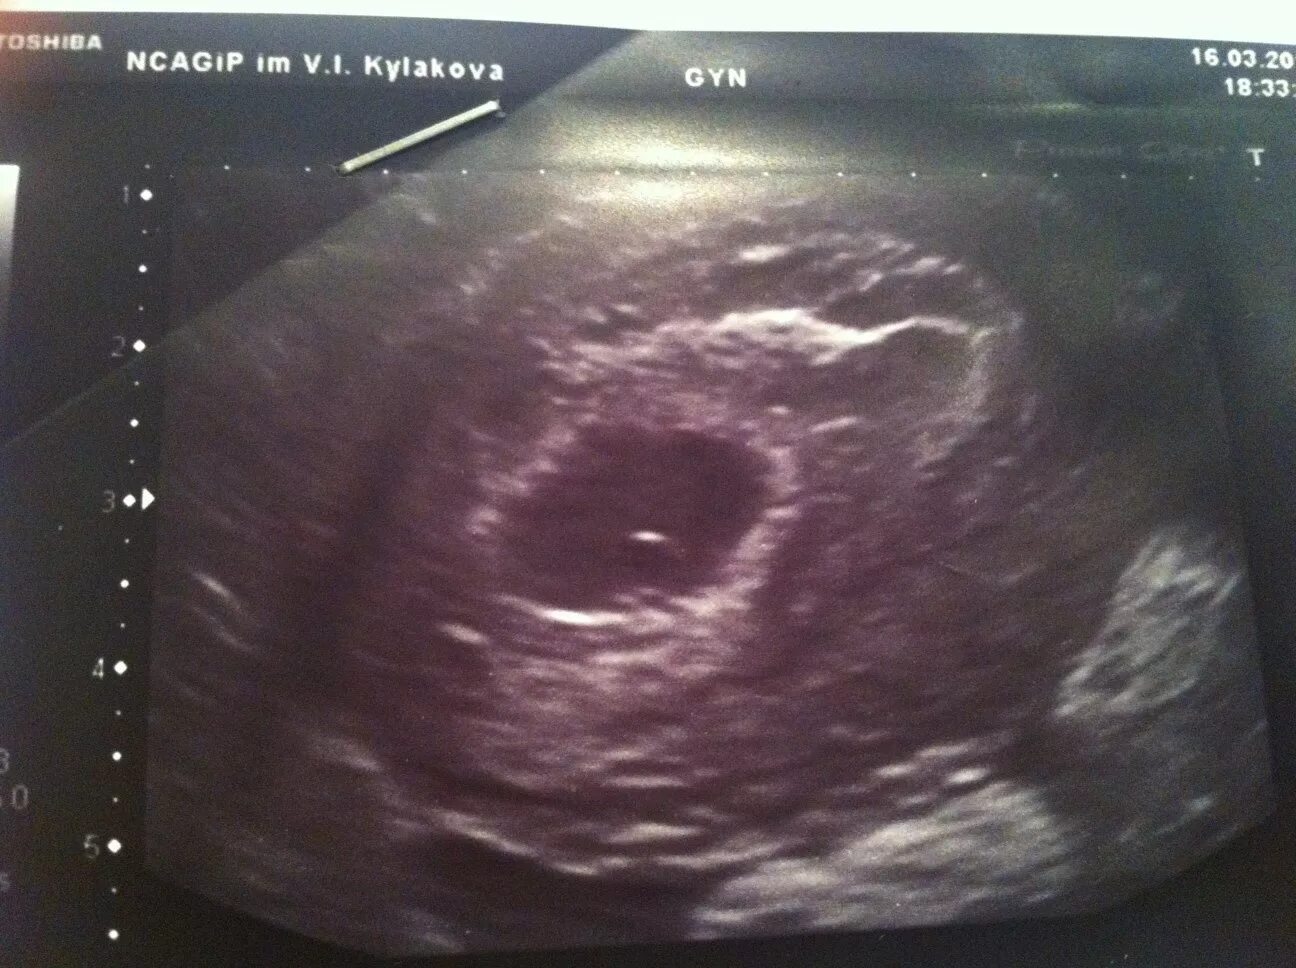

3 нед 2 дня